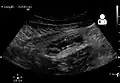

A CT scan demonstrating acute appendicitis (note the appendix has a diameter of 17.1 mm and there is surrounding fat stranding).

A fecalith marked by the arrow that has resulted in acute appendicitis.

Where it is readily available, computed tomography (CT) has become frequently used, especially in people whose diagnosis is not obvious on history and physical examination. Although some concerns about interpretation are identified, a 2019 Cochrane review found that the sensitivity and specificity of CT for the diagnosis of acute appendicitis in adults was high.[63] Concerns about radiation tend to limit use of CT in pregnant women and in children, especially with the increasingly widespread usage of MRI.[64][65]

The accurate diagnosis of appendicitis is multi-tiered, with the size of the appendix having the strongest positive predictive value, while indirect features can either increase or decrease sensitivity and specificity. A size of over 6 mm is both 95% sensitive and specific for appendicitis.[66]

However, because the appendix can be filled with fecal material, causing intraluminal distention, this criterion has shown limited utility in more recent meta-analyses.[67] This is as opposed to ultrasound, in which the wall of the appendix can be more easily distinguished from intraluminal feces. In such scenarios, ancillary features such as increased wall enhancement as compared to adjacent bowel and inflammation of the surrounding fat, or fat stranding, can be supportive of the diagnosis. However, their absence does not preclude it. In severe cases with perforation, an adjacent phlegmon or abscess can be seen. Dense fluid layering in the pelvis can also result, related to either pus or enteric spillage. When patients are thin or younger, the relative absence of fat can make the appendix and surrounding fat stranding difficult to see.[67]